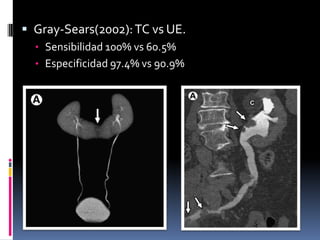

 Gray-Sears(2002): TC vs UE.

• Sensibilidad 100% vs 60.5%

• Especificidad 97.4% vs 90.9%

ANNE M. SILAS, MD, FRCPC. EVALUATING THE UROTHELIUM WITH CT UROGRAPHY: ARE WE THERE YET?. SEMINARS IN ROENTGENOLOGY. 2009.

ZACHARY W. WASHBURN, MD, JONATHAN R. DILLMAN, MD, RICHARD H. COHAN. COMPUTED TOMOGRAPHIC UROGRAPHY UPDATE:AN EVOLVING URINARY TRACT IMAGING MODALITY.

SEMIN ULTRASOUND CT MRI 30:233-245 © 2009 ELSEVIER INC.